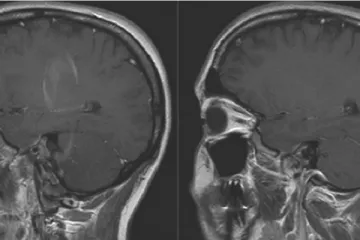

PROBOJ U ISTRAŽIVANJU: / Slovenski znanstvenici otkrili da zika isključivo napada živčane stanice mozga